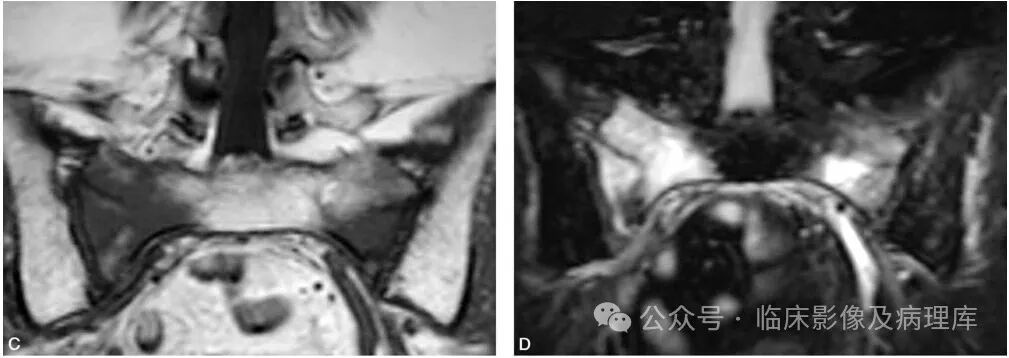

A.X线平片显示左胫骨上段凸向前方弯曲,上中1/3骨干有囊状破坏呈不均匀骨化并有V字征(小箭头),中段骨髓内亦有少量骨化(大黑箭头);B.左小腿中下段凸向前方弯曲,中下1/3交界处有横行骨折裂缝(大黑箭头),骨髓均匀高密度骨化,其中有囊状破坏并出现“V”形征(小黑箭头)病理证实